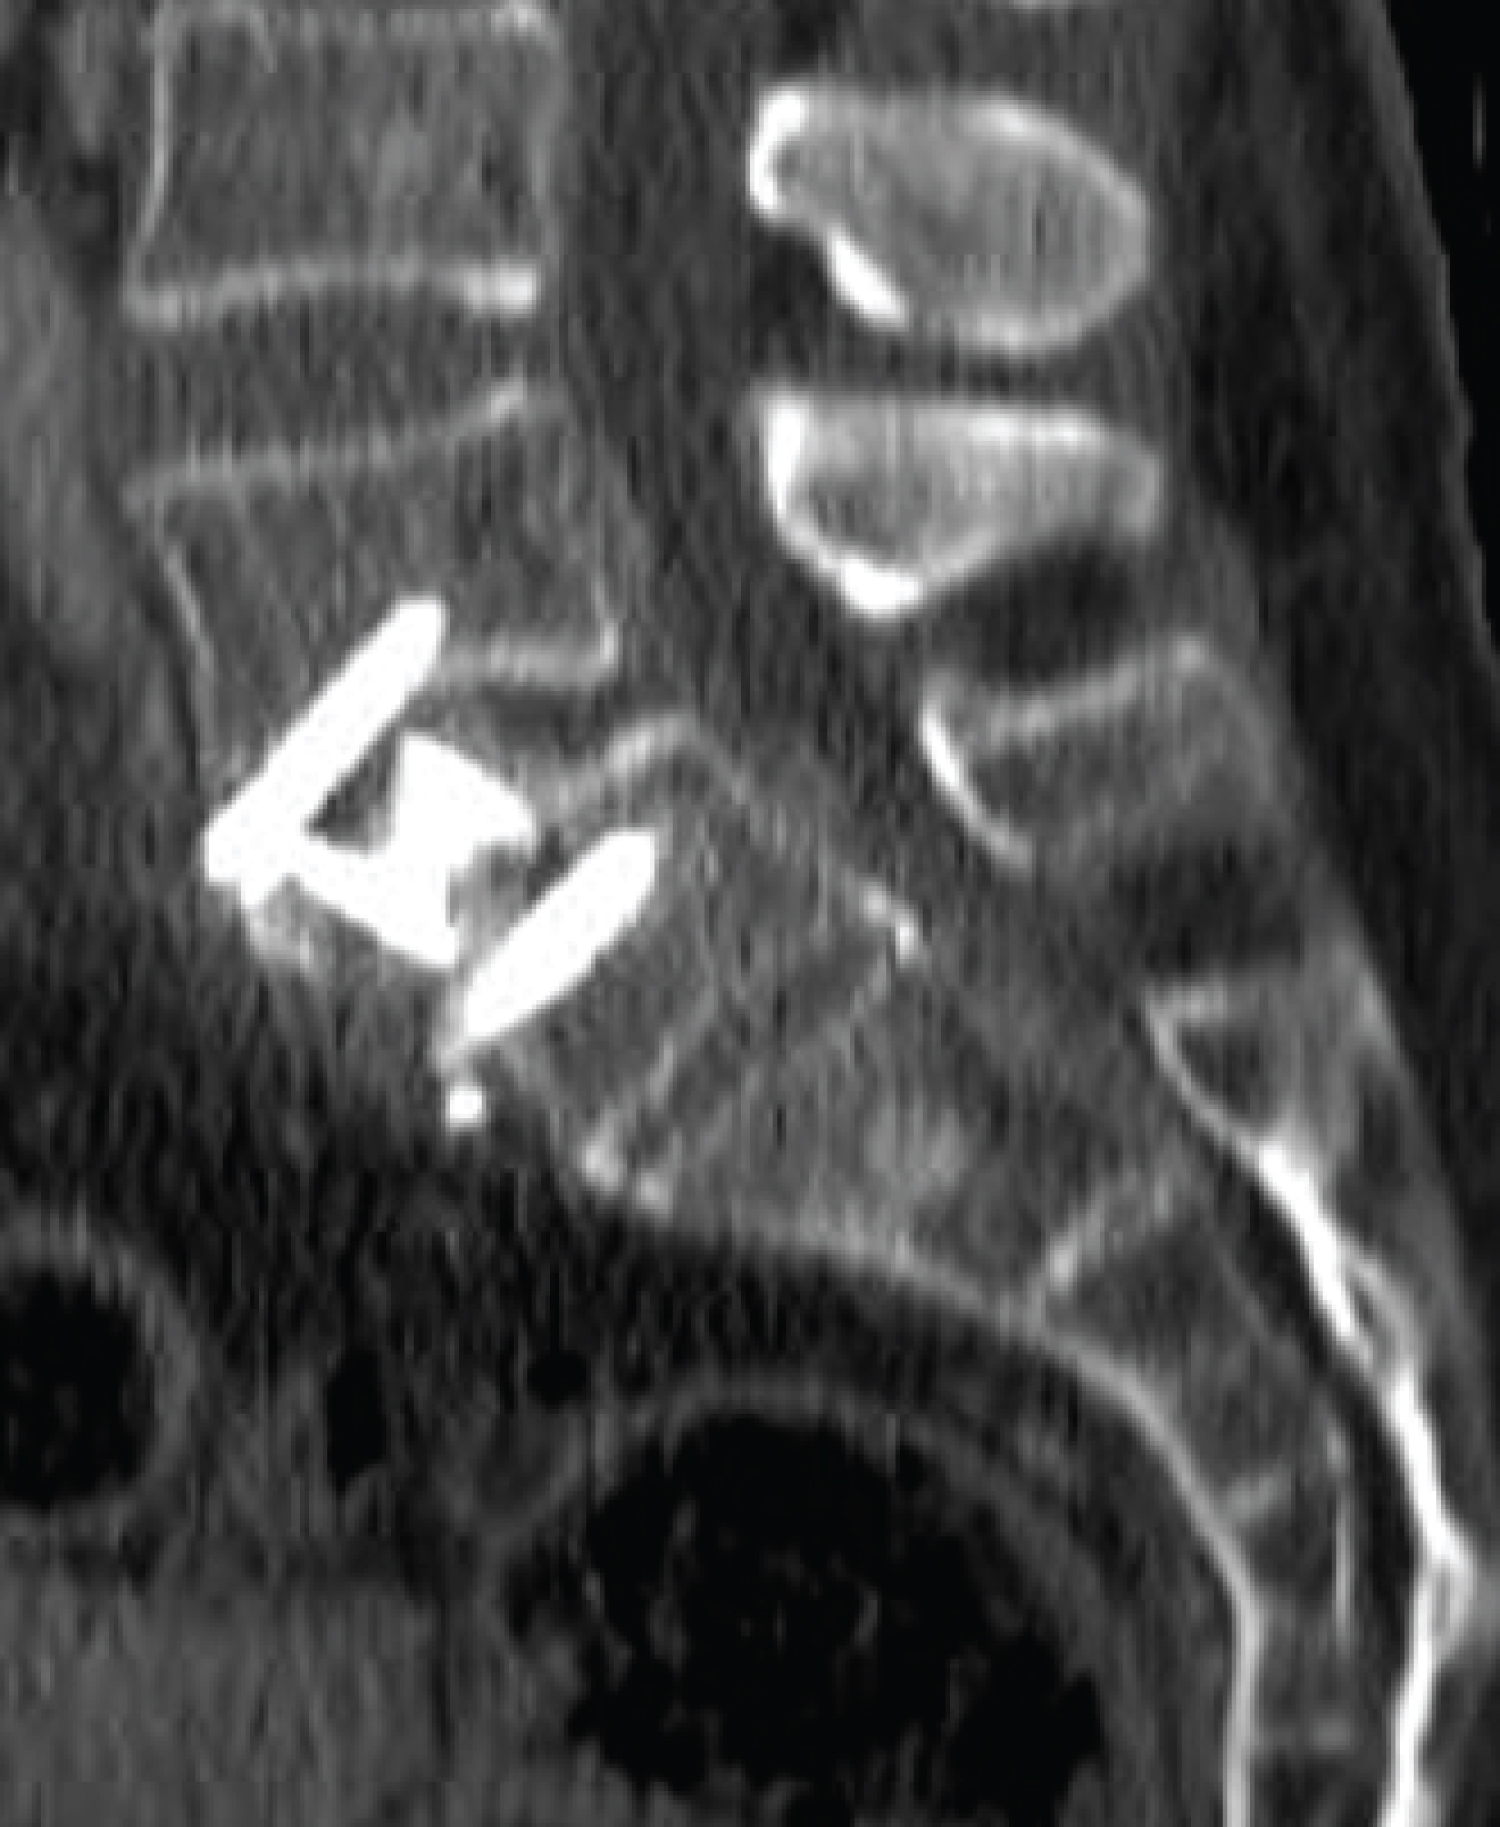

A 63-year-old woman consulted to the emergency room for abdominal pain and nausea. She had undergone an L5-S1 ALIF surgery via an anterior lumbar approach 5 days prior in another hospital. Blood tests showed no alterations and Plain X-Rays showed feces in the descending colon, without loosening of the implant. A CT scan was performed, which showed abundant intraabdominal liquid and a pneumoperitoneum (Figure 1 and Figure 2).

Figure 1: Preoperative abdominal CT scan with diffuse pneumoperitoneum. View Figure 1